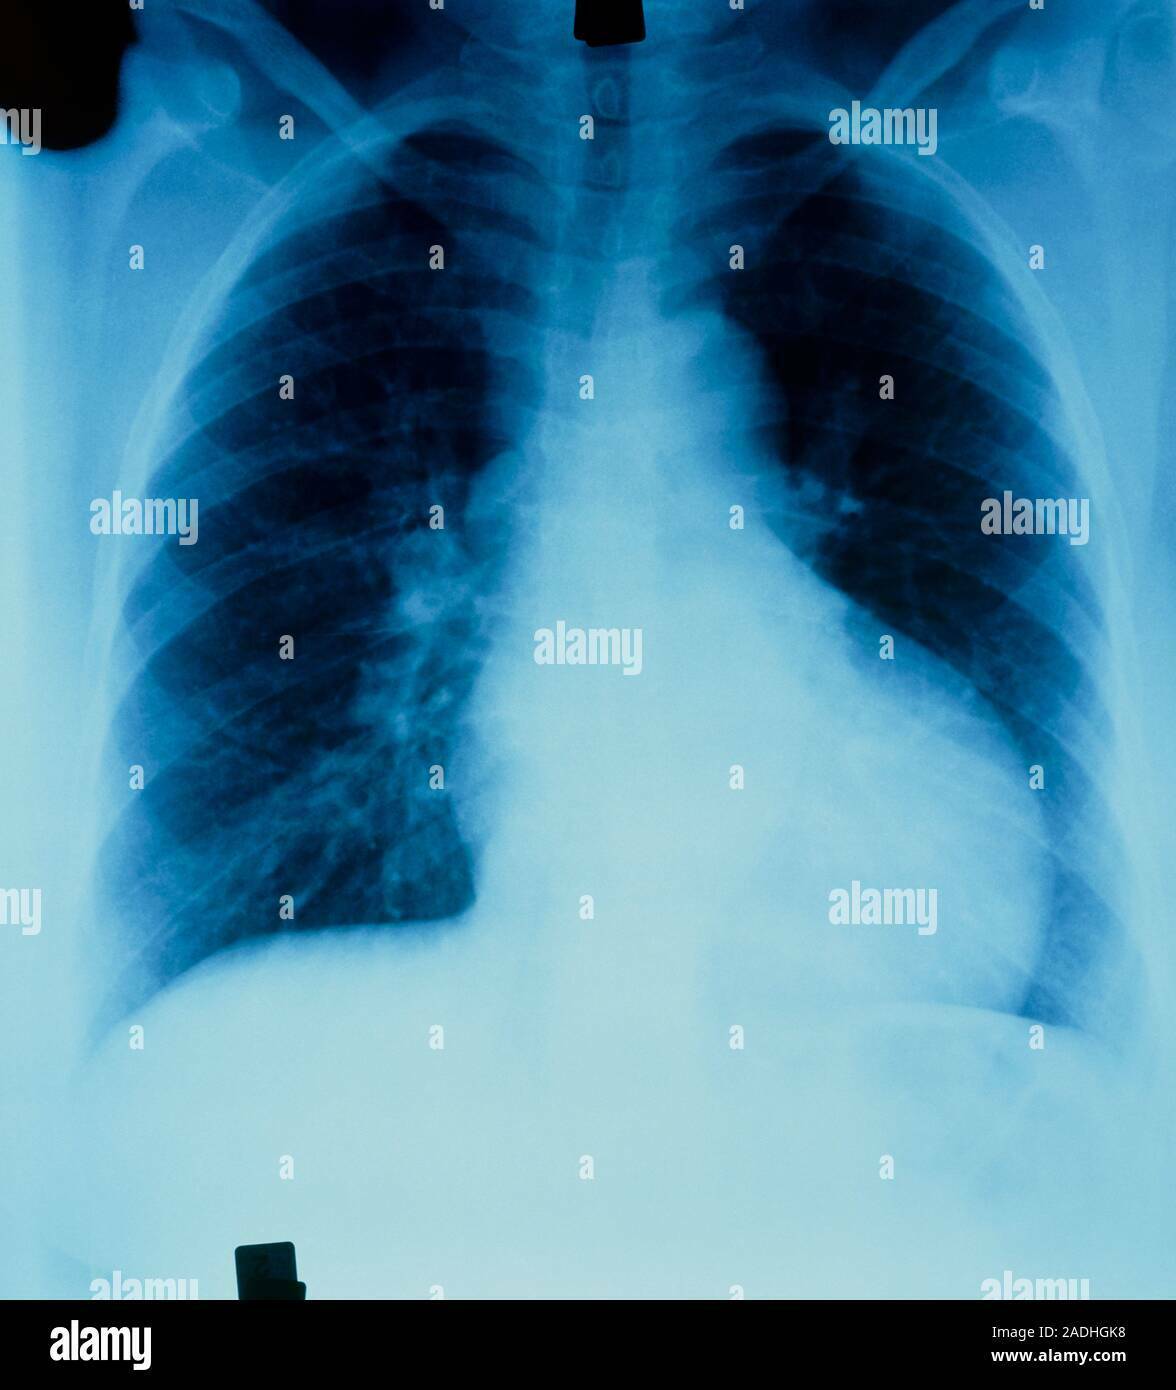

Quais são os limites do coração no Raiox? Deve respeitar a linha hemiclavicular esquerda, ser centralizado no mediastino e com artérias e veias pulmonares visíveis

Quais são as doenças intersticiais que cursam com o espessamento linear/reticular e quais são seus achados radiológicos? São fibrose pulmonar, saircose, artrite reumatóide, asbestose e silicone (pneumoconioses); Trama vascular, espessamento como estrias, sem broncograma aéreo e sinal da silhueta

Quais são as doenças intersticiais que cursam com o espessamento nodular e quais são seus achados radiológicos? São pneumonias, EAP, Asma, DPOC ; Sinal da silhueta, Sinal do Broncograma aéreo, pulmão não aerado (mais branco). Não se vê trama vascular na área consolidada.